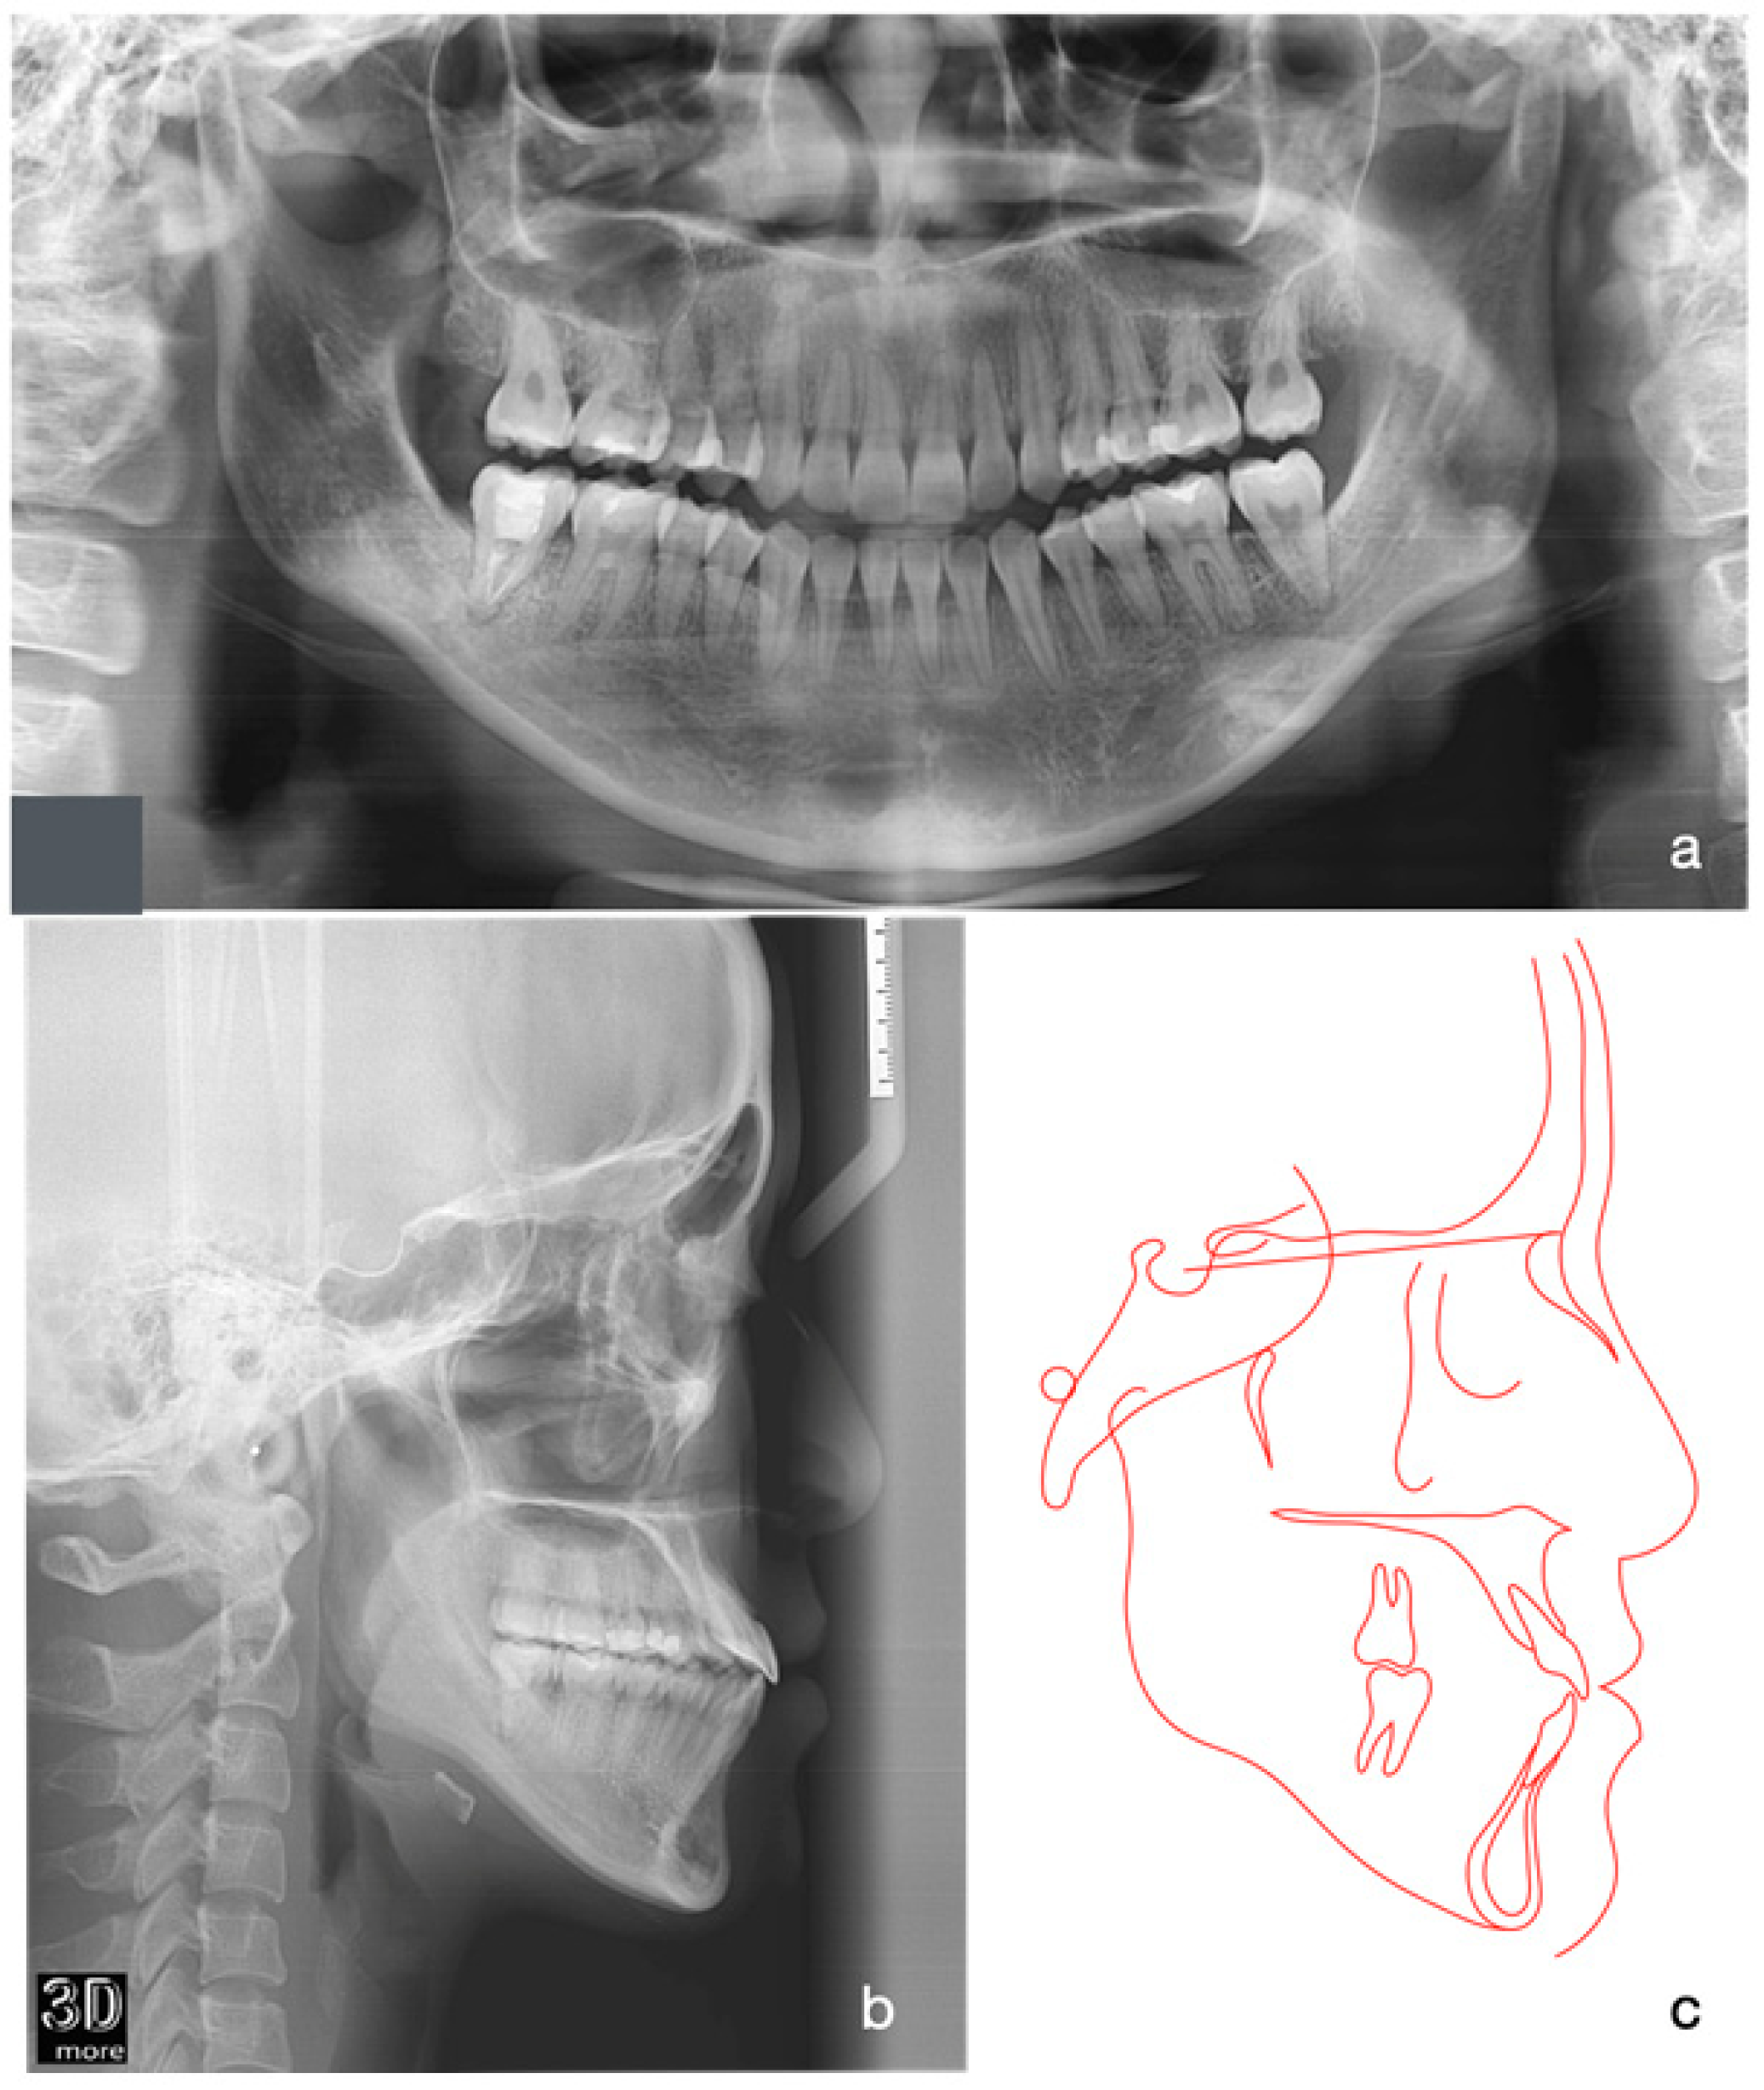

2.1. Diagnosis and Aetiology

2.4. Treatment Progress